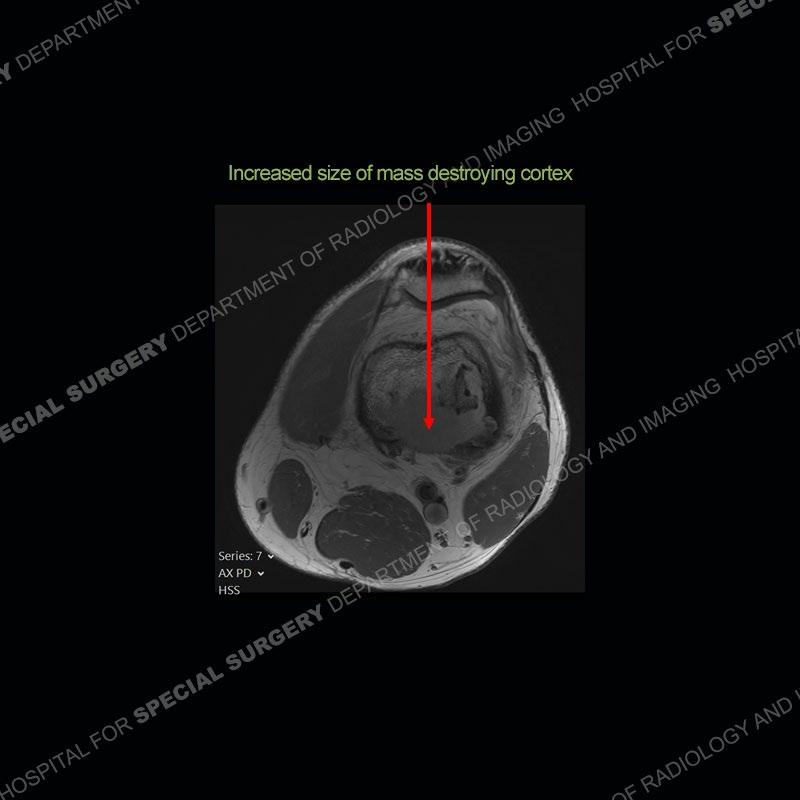

Subsequent imaging of 2024 demonstrates increased size of the mass lesion about the infarct of the distal femur with destruction of the posterior cortex.

Diagnosis: Sarcomatous Transformation of Medullary Infarction

Bone infarcts are fairly common to find and for the most part are asymptomatic. These lesions most typically become symptomatic when they extend to the end of the bone and are associated with subchondral fracture and collapse. Complications of infarct such as infection or sarcomatous transformation are known to occur but because they are extremely rare, exact incidence is not known. Interestingly, most reported cases of sarcomatous transformation occur in middle aged men and about the knee as in this case. Sarcomatous transformation of an infarct can be suggested on radiographs if the infarct goes from being well defined to less well defined. On cross sectional imaging, a destructive mass, as seen in this case, is seen to take the place of the otherwise typical appearance of an infarct. The sarcoma most commonly is an MFH ( more recently delineated as UPS or undifferentiated pleomorphic sarcoma) or osteosarcoma. These sarcomas unfortunately carry a very poor prognosis.